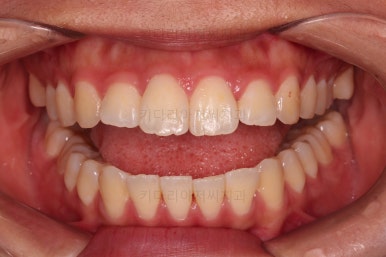

5. 마무리와 치료 종료

마무리가 잘 되었습니다.

큰 문제는 없었지만, 약간 삐뚤었던 치열이 가지런하게 정렬이 잘 되었고요.

맞물림도 매우 좋고, 뻗친 앞니 각도도 매우 좋아졌습니다.

입 안의 모습만 보면 최상급의 마무리가 되었고요.

이제 얼굴모습 변화 비교해 보겠습니다.

6. 전후 사진 비교

입매가 매우 좋아졌습니다.

과연 11개월의 치료결과가 맞나 싶을 정도로 깜짝 놀랄만큼 만족스러운 치료결과였는데요.